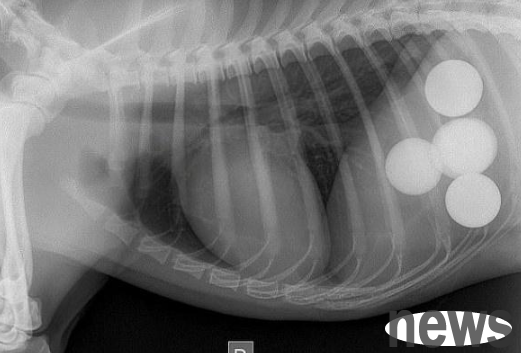

However, after half a day, the dog's abdomen still did not dissipate. The owner then realized that the dog must have swallowed something by mistake, which caused it to be unable to digest. Therefore, he took the dog to the hospital for a physical examination. It turned out that several ring-shaped things were found in the belly, but the doctor could not identify what they were in a short period of time.

After more than 2 hours of hard work, the doctor finally expelled the ring-shaped object from the dog's body. It turned out that the dog had swallowed five golf balls by mistake and was unable to digest them. Golf balls are usually made of hard rubber or plastic, not to mention that the dog also swallowed them all, so it is normal for the dog to be unable to digest them.